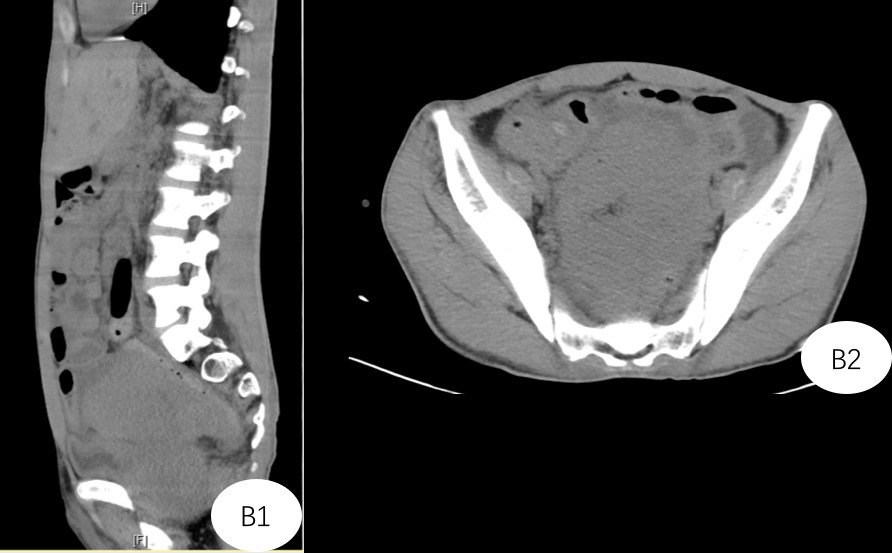

术前诊断:腹盆腔巨大淋巴瘤、肠瘘、肾积水、重度营养不良。入院后患者腹部膨隆速度较快,腹围进行性增长,再次进行CT显示肿瘤占据了整个盆腔,两侧的髂血管、输尿管受挤压出现狭窄,并且与前列腺、膀胱后壁、直肠前壁、小肠等重要器官关系密切。

B1+ B2:CT提示患者肿瘤占据盆腔,与直肠、膀胱、前列腺关系不清楚。加上患者骨盆小,术中暴露是手术的难点